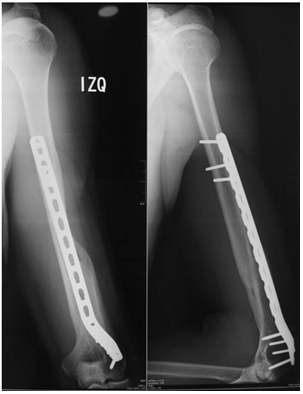

In case of a radial a radial nerve injury in a closed fracture, no routine exploration was performed in the proximal portion, except in cases of exposed fracture where it was necessary at the time of debridement to determine the interposition of the radial nerve. A soft brachiopalmar immobilization and a palmar hand splint were applied in cases where the nerve was injured. The clinical control was carried out at two weeks, the second month, the fourth month and the postoperative year. Rehabilitation was started at the second postoperative week (Figure 2).